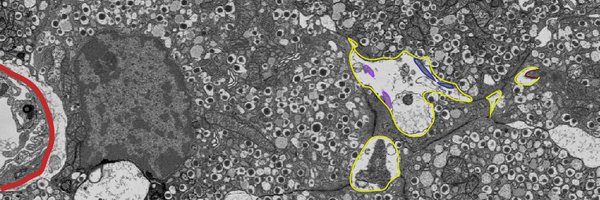

Diabetologia cover